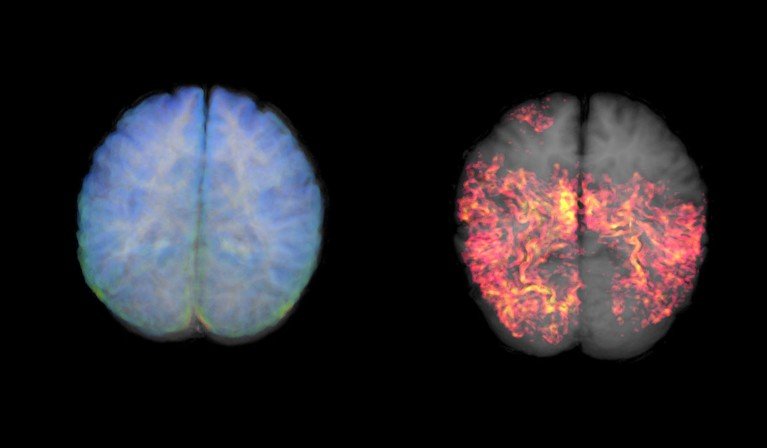

A blood test measuring levels of tau protein is almost 98% accurate in ruling out Alzheimer’s disease in individuals with cognitive impairments.Credit: Thomas Deerinck, NCMIR/Science Photo Library

إن اختبار الدم الذي يقيس مستويات بروتين تاو دقيق بنسبة 98٪ تقريبًا في استبعاد مرض الزهايمر لدى الأفراد الذين يعانون من إعاقات إدراكية.الائتمان: توماس ديرينك، NCMIR / مكتبة الصور العلمية

يقوم التصوير بالرنين المغناطيسي الملون (MRI) بمسح دماغ سليم (يسار) ودماغ يحتوي على مجموعات من بروتينات تاو (يمين). الائتمان: معهد مارك وماري ستيفنز للتصوير العصبي والمعلوماتية/مكتبة الصور العلمية